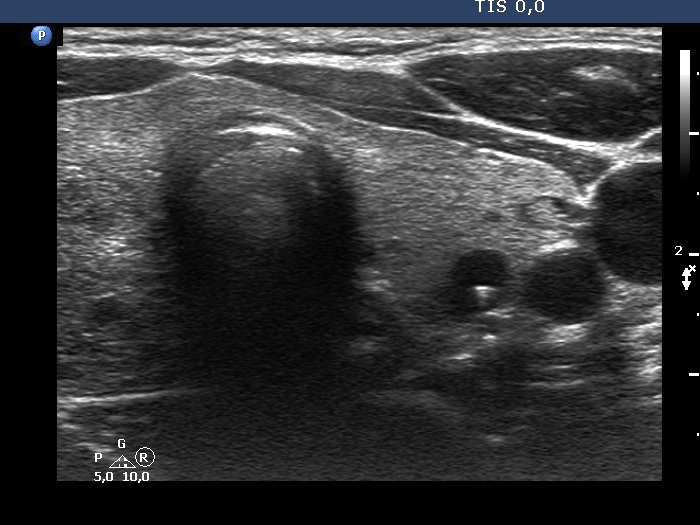

Ultrasonography. The thyroid was composed of numerous discrete lesions of various echogenicities. There was a partly cystic nodule in the upper-ventral part of the right lobe. The left lobe contained several cystic areas having comet tail artifacts.

Aspiration cytology of the largest nodule in the right lobe resulted in benign colloid goiter.